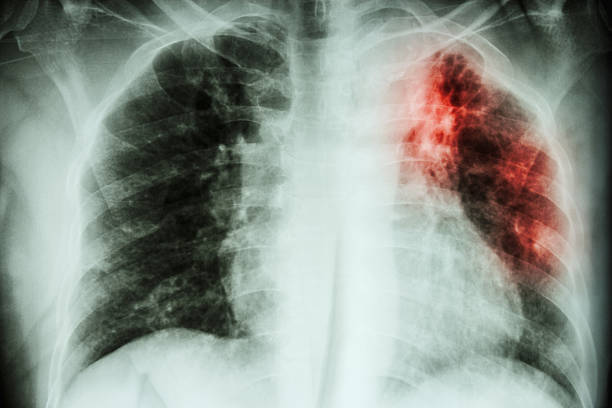

Туберкулезный процесс представляет собой болезненное самочувствие, которое сложно поддается лечению. Пациенты, сумевшие побороть недуг, отмечают, что противотуберкулезная терапия могла длиться у них годами, оставив после себя ряд осложнений и негативных последствий. Почему так сложно избавиться от болезни? Дело в том, что микобактерии туберкулеза обладают многоуровневой защитой, а поэтому резистентные к большинству противобактериальных препаратов, резким температурным перепадам, ультрафиолетовому излучению и тому подобное. К тому же, после проникновения в человеческий организм, они быстро снижают функцию иммунной системы, что делает невозможным процесс избавления от них. Туберкулез нуждается в массовой профилактике, так как ежегодно уносить миллионы жизней людей, не имеющих специфической защиты от инфекции.

- сегодня в некоторых странах, которые развиваются, туберкулез приобрел эпидемиологический характер, быстро распространяясь как среди взрослого населения, так и в детских коллективах;

- если верить статистике, то пятая часть населения планеты является зараженной этой инфекцией;

- ежегодно в мире от туберкулеза умирает около 2,5 млн. человек;